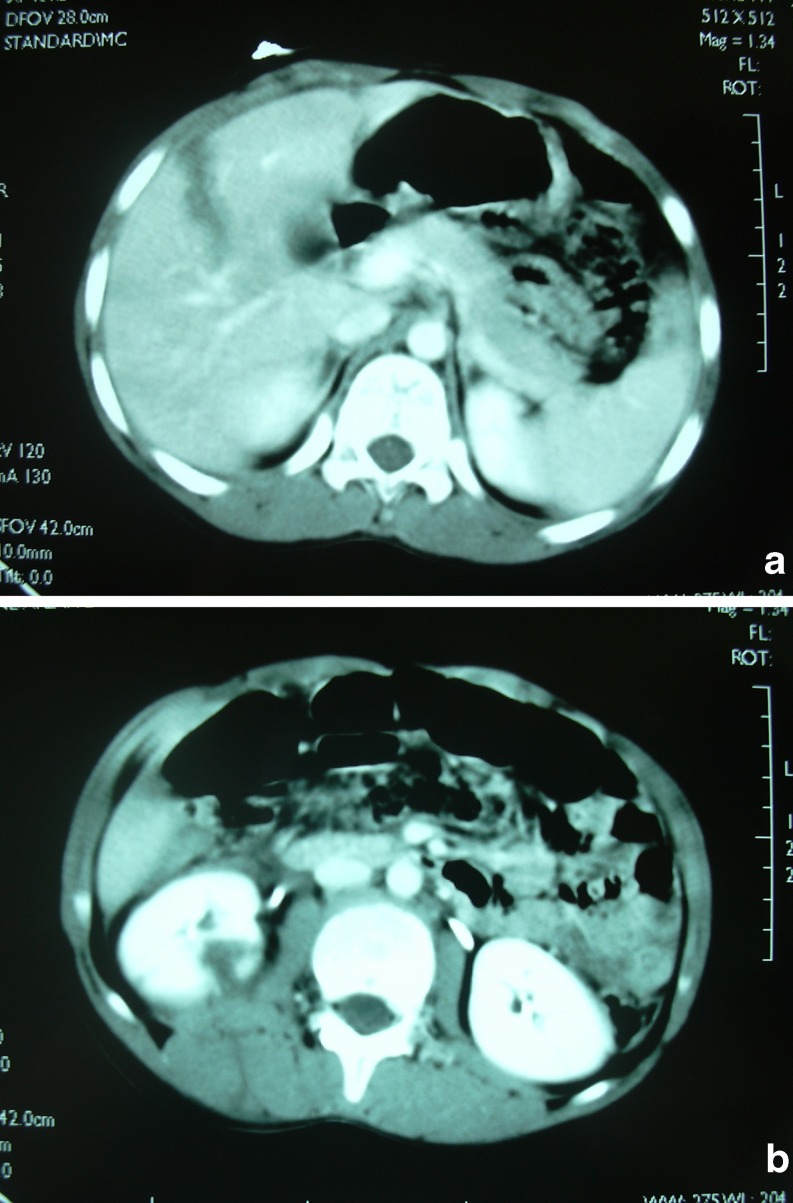

Fig. 2.

CT scan shows a laceration of the right hepatic lobe (a) and right lower renal pole, fracture of processus transversus of L2 (b)

A previously healthy 10-year-old boy presented to our hospital after a gunshot wound to the right lumbar area near the vertebral column. No existing wound was identified. Initial vital signs revealed a heart rate of 100 beats/min and blood pressure of 90/50 mmHg. The right upper and lower abdomens were tender. On the right lumbar area at the level of L2, there was a bullet entry. The hemoglobin level was 12.4 g/dl and white blood cell count was 19,400 103/μl. Chest X-ray revealed no pathology, and no free air was detected on the upright abdominal X-ray. The bullet could be identified at the right side of L2 (Fig. 1). Computed tomography (CT) scanning performed after contrast media ingestion revealed a laceration of the right hepatic lobe (Fig. 2a) and right lower renal pole, fracture of processus transversus of L2 and also a hematoma in the psoas muscle and perirenal area and additionally free air (Fig. 2b). No intestinal contrast leakage was observed on late follow-up scan. Intravenous fluids, tetanus toxoid, and second-generation cephalosporin antibiotic were administered. This patient was admitted to the intensive care unit. In this unit, blood pressure monitoring, pulse rate, serial hemoglobin, oxygen saturation, and repeated abdominal examinations were routinely performed on this patient. Control Hb levels of the patient were not lower than 12 g/dl. The patient recovered well and was discharged on the sixth day of hospital admission.